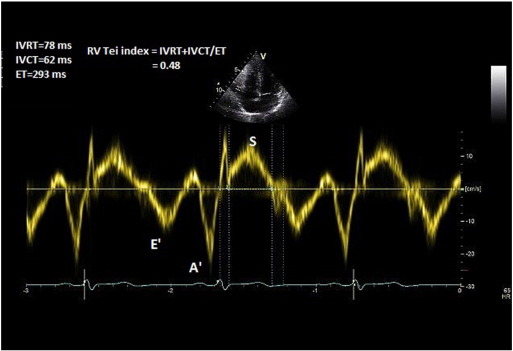

8. Tei index and TR measured PASP

8.1. Method

In the apical 4-chamber view, TDI is deployed on the RV free wall and a 3–5 mm pulse wave Doppler is obtained approximately 1 cm from the tricuspid annulus. Isovolemic contraction time (IVCT), isovolemic relaxation time (IVRT), and ejection time (ET) of the RV are then measured (Fig. 8 ). Alternatively, these measures could be obtained from CW Doppler across the RV inflow/TR jet. Tei index is measured by the formula: Tei Index (RV) = IVRT + IVCT/ET.

Fig. 8

Fig. 8.

Measurement of Tei index.

8.2. Common pitfalls

The method was studied in small groups of patients and has not yet been validated in larger sample sizes [28]  and [29] . Tei index is, however, proven to prognosticate patients with pulmonary hypertension [30] .